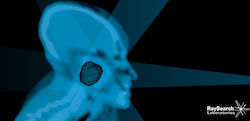

From the start, RayStation was designed to handle 4-D adaptive radiation therapy and the new release includes groundbreaking features in this field. Using advanced deformable registration algorithms RayStation 2.5 allows the users to perform dose-tracking. This offers the possibility to perform accurate dose accumulation of any delivered or planned dose to any patient geometry while using any combination of computed tomography (CT), magnetic resonance (MR), positron emission tomography (PET) and 4-D CT data sets. RayStation is the first treatment planning system that lets the clinicians monitor the impact of a changing patient geometry as the treatment progresses, and easily adjust the treatment in the same system. The dose-tracking functionality was developed in collaboration with Princess Margaret Hospital in Toronto, Canada, and is available for installation in Europe but is pending regulatory clearance in the United States and Canada.